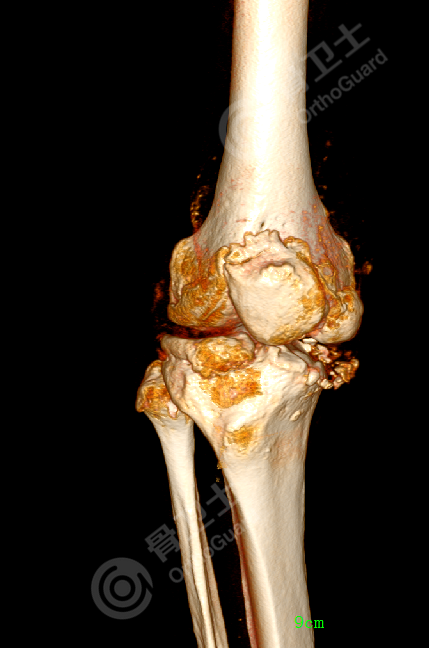

▲患者术前X线片

查体发现,患者双膝关节肿胀,膝关节内翻畸形,右侧明显,右膝关节内侧间隙压痛明显,右膝关节屈曲活动度受限,主动伸屈活动范围10-90度,肌张力正常,双膝反射正常,双侧踝反射正常,双下肢感觉良好,末梢皮色红润。

综合患者影像资料,诊断为双膝骨关节炎。

考虑到患者双膝骨关节炎退变严重,右膝为重,长时间的膝内翻畸形,导致右膝关节双侧副韧带松弛,关节不稳;双膝关节活动度差,关节活动受限严重,股四头肌及膝关节后侧肌力萎缩;内侧胫骨平台软骨磨损严重,并内侧骨质缺损,各种因素叠加,增加了手术难度。